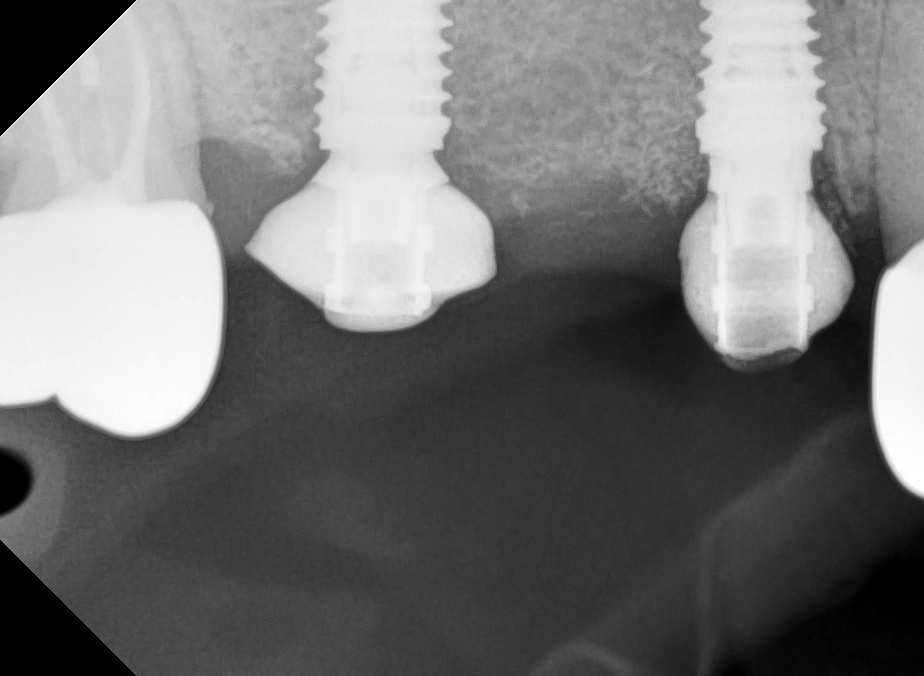

Федотов Руслан Валерьевич – высококвалифицированный стоматолог-хирург с более чем десятилетним стажем работы, который посвятил свою профессиональную деятельность помощи людям в достижении здоровой и красивой улыбки. За время своей практики он успешно освоил и внедрил в работу множество современных методик и систем имплантации, что позволяет ему находить индивидуальный подход к каждому пациенту, учитывая все особенности и потребности.

В своей работе Руслан Валерьевич использует только современное оборудование и материалы, соответствующие международным стандартам качества. Он мастерски владеет различными методиками имплантации, включая одноэтапные протоколы и компьютерную навигацию. Особое внимание врач уделяет безболезненности процедур и комфортному восстановлению пациентов после операций.